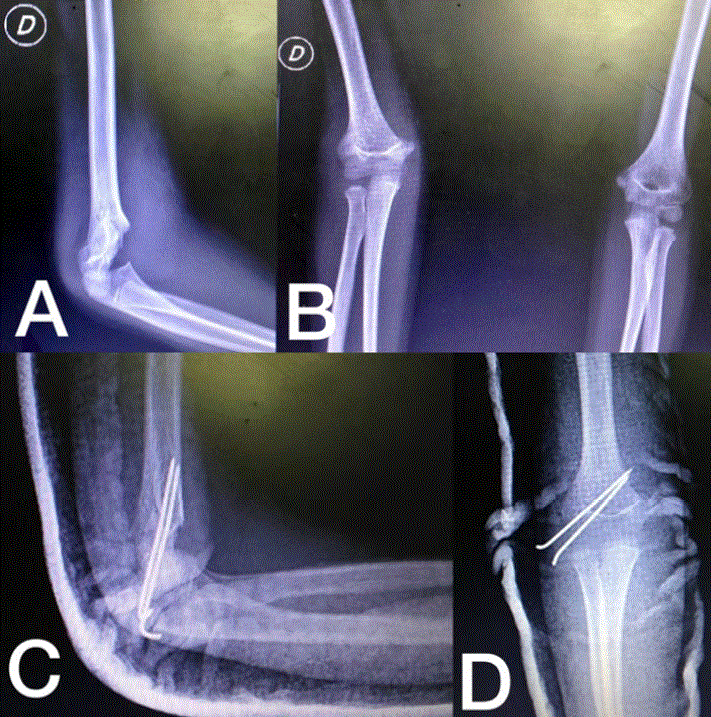

En la Figura 9 se puede ver una fractura supracondílea Gartland IV y la reducción y fijación con 3 pines percutáneos, dos laterales y uno medial y en la Figura 10, una fractura supracondílea Gartland II con desplazamiento posteromedial con reducción cerrada, fijación percutánea con dos pines laterales e inmovilización con férula.